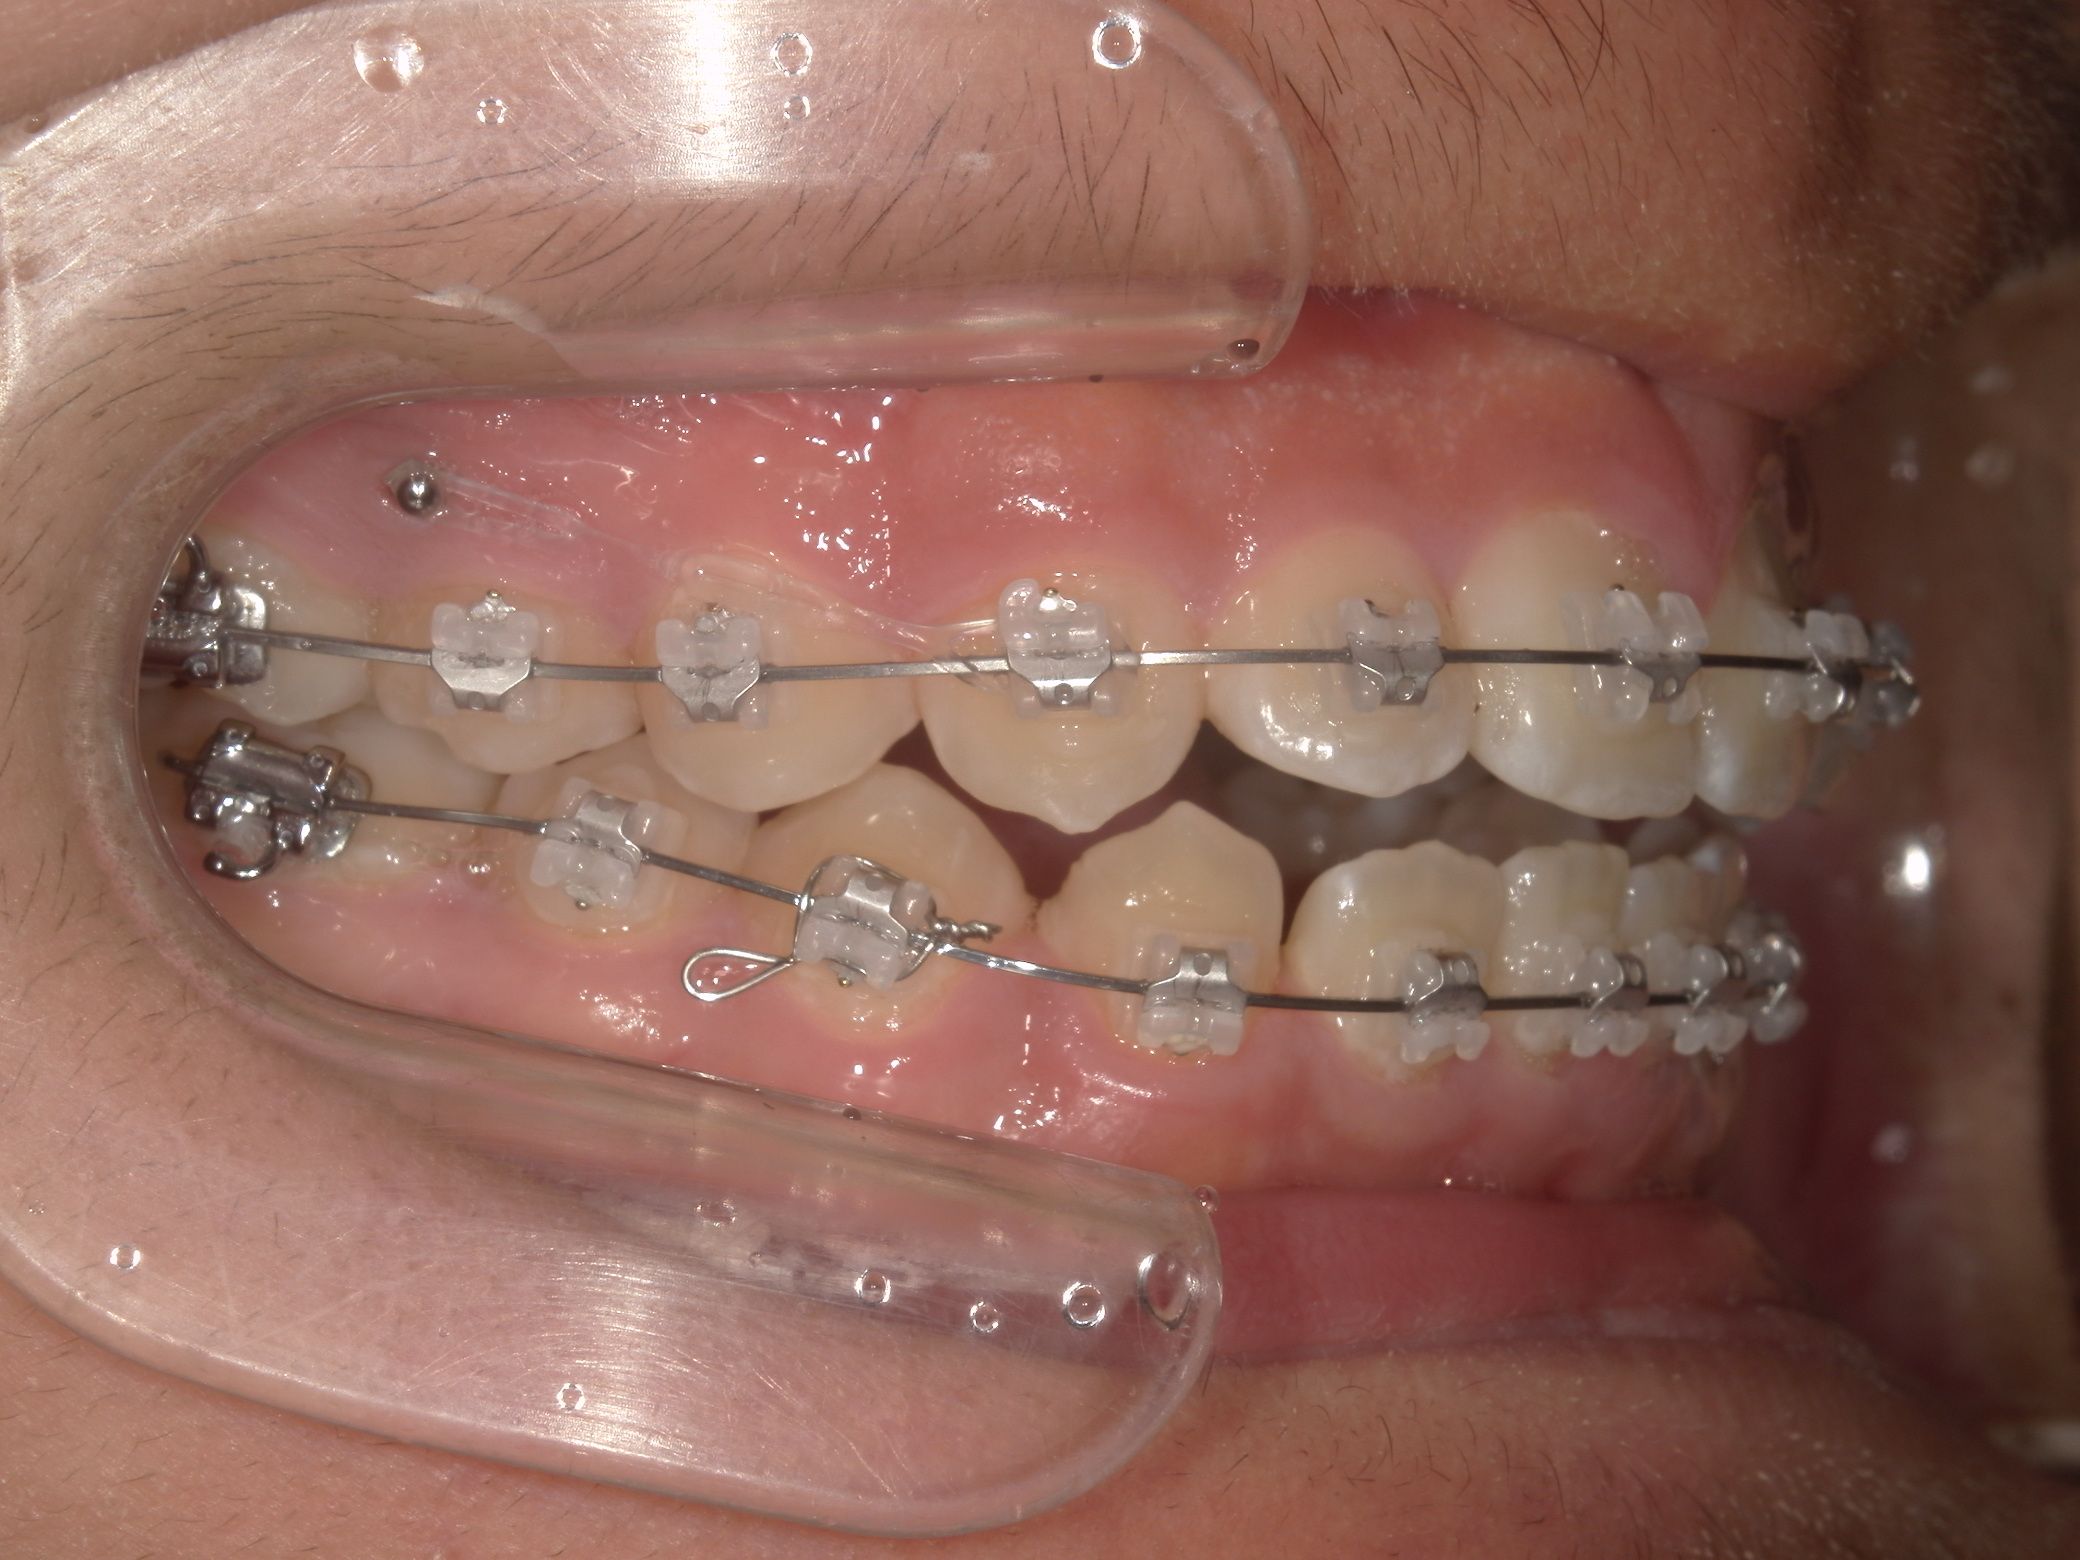

リカバリー症例の初診時の口腔内|奈良の矯正歯科

初診時

抜歯矯正1年後の口腔内|奈良の矯正歯科

治療1年後

抜歯矯正完了後の口腔内|奈良の矯正歯科

治療完了

他院で非抜歯矯正を受け、歯並びは改善したものの、口元の突出感が残ったまま治療が終了。当院で精密検査を行った結果、上下4本の抜歯によるリカバリー治療が必要と判断しました。